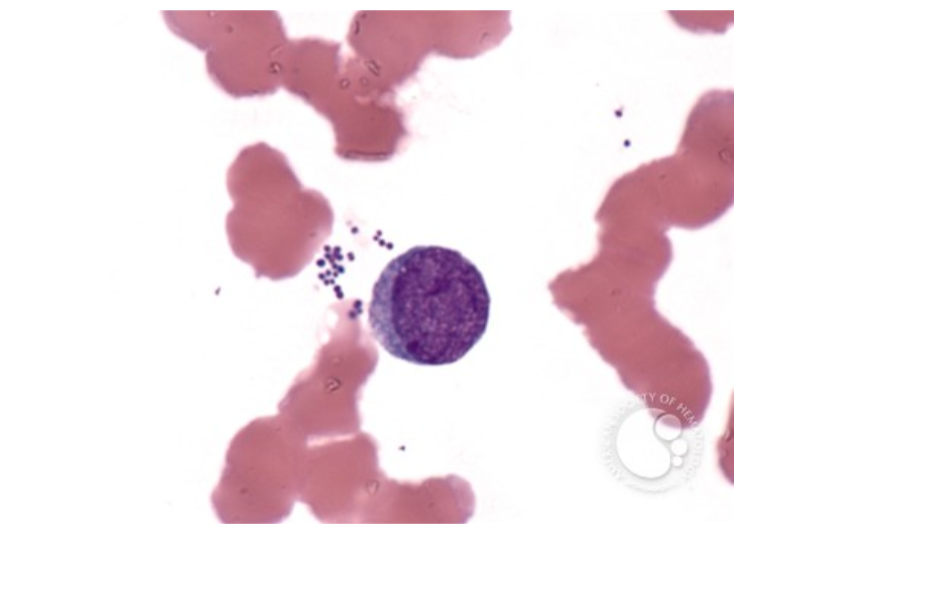

A previously healthy 35-year-old female complains of loss-of-appetite, vomiting, fever in irregular cycles and headaches.

Recent travel history revealed that she traveled to the WHO African Region.

See below for the blood count results, an image of the peripheral blood smear and the BinaxNow quick test result.

malaria